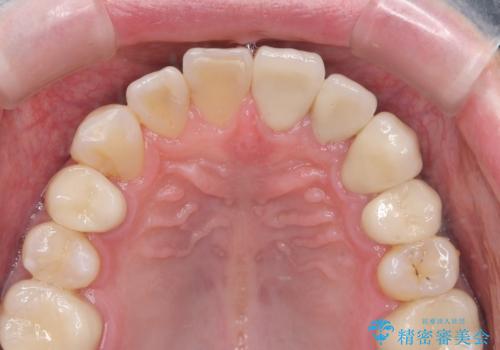

セラミック治療を行うことで、虫歯の再発リスクをおさえ、審美的な前歯の見た目を回復することができました。